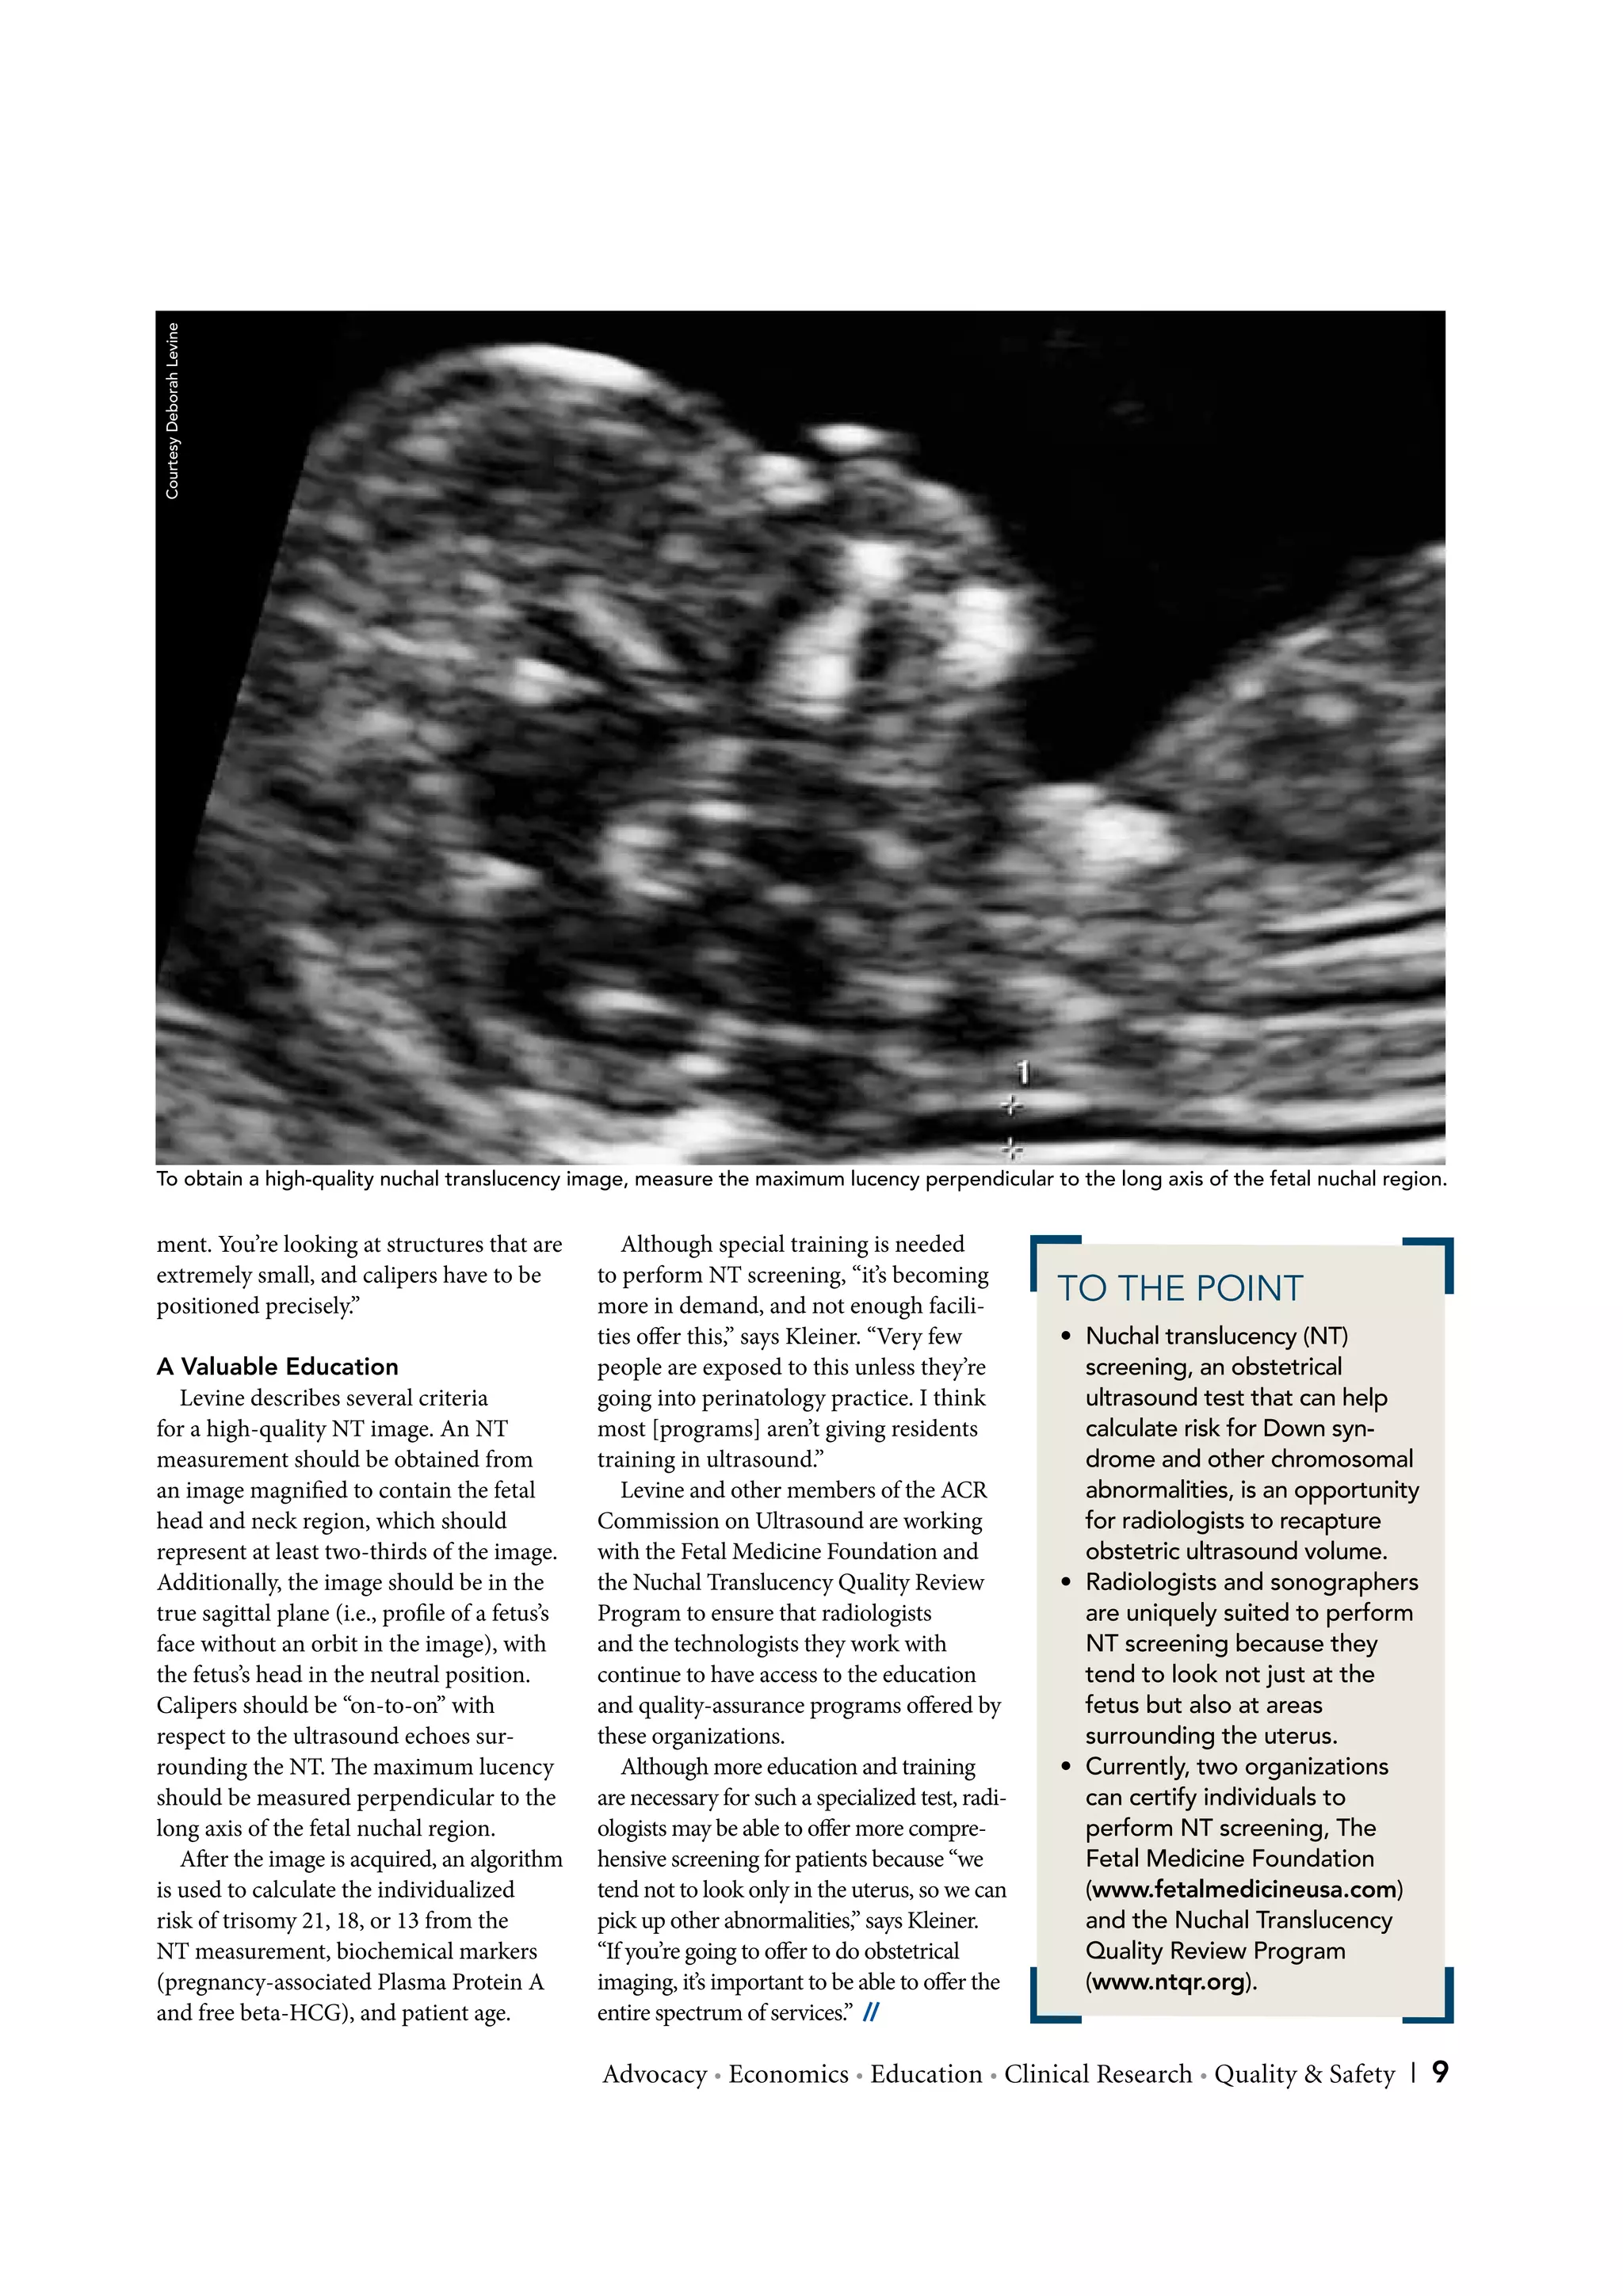

To obtain a high-quality nuchal translucency image, measure the maximum lucency perpendicular to the long axis of the fetal nuchal region.

Levine describes several criteria             going into perinatology practice. I think            ultrasound test that can help

for a high-quality NT image. An NT               most [programs] aren’t giving residents              calculate risk for Down syn-

measurement should be obtained from              training in ultrasound.”                             drome and other chromosomal

an image magni ed to contain the fetal              Levine and other members of the ACR               abnormalities, is an opportunity

head and neck region, which should               Commission on Ultrasound are working                 for radiologists to recapture

represent at least two-thirds of the image.      with the Fetal Medicine Foundation and               obstetric ultrasound volume.

Additionally, the image should be in the         the Nuchal Translucency Quality Review             • Radiologists and sonographers

true sagittal plane (i.e., pro le of a fetus’s   Program to ensure that radiologists                  are uniquely suited to perform

face without an orbit in the image), with        and the technologists they work with                 NT screening because they

the fetus’s head in the neutral position.        continue to have access to the education             tend to look not just at the

Calipers should be “on-to-on” with               and quality-assurance programs o ered by             fetus but also at areas

respect to the ultrasound echoes sur-            these organizations.                                 surrounding the uterus.

rounding the NT. e maximum lucency                  Although more education and training            • Currently, two organizations

should be measured perpendicular to the          are necessary for such a specialized test, radi-     can certify individuals to

long axis of the fetal nuchal region.            ologists may be able to o er more compre-            perform NT screening, The